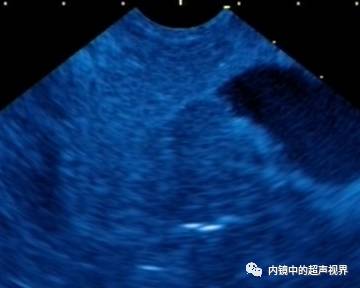

再说伪彩,它把黑白图像处理成黑橙、黑绿、黑蓝、黑粉等图像,一定程度上改变了图像的视感,类似于FICE、iSCAN等后处理光学染色功能,萝卜白菜各有所爱,喜欢哪个直接拿走。